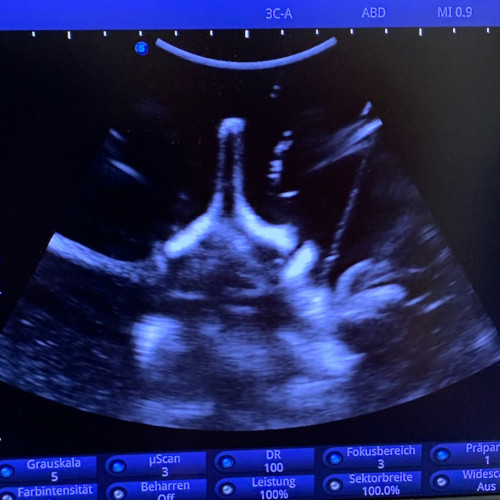

Ultraschall-gezielte Infiltrationsbehandlung – Es handelt sich dabei um eine Ultraschall-gezielte Infiltration ohne Strahlenbelastung. Dadurch können Schmerzen schnell und effektiv behandelt werden. Diese Infiltration kann bei mir in der Ordination durchgeführt werden.

- Ultraschallgezielte Infiltration der Facettengelenke, Nervenwurzeln, ISG und epidurale Flutungen von caudal